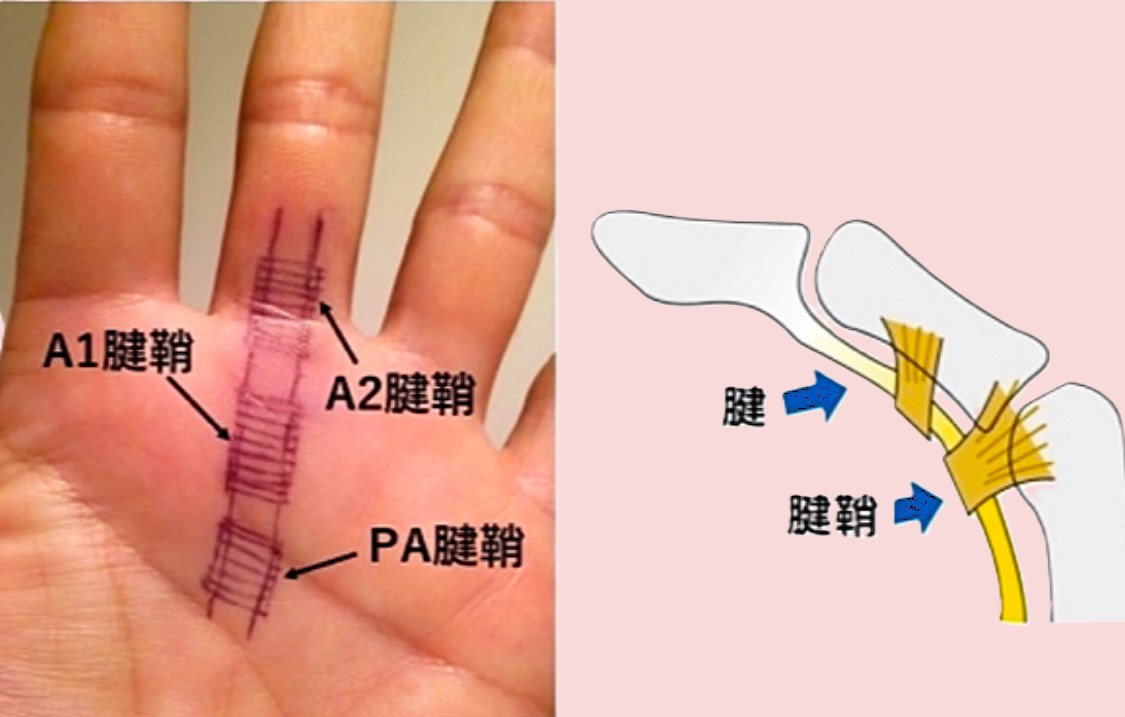

ばね指

指の付け根に起こるばね指=腱鞘炎に対して超音波ガイド下に正確にA1腱鞘に針を正確に刺入しステロイドやPRPを注入します